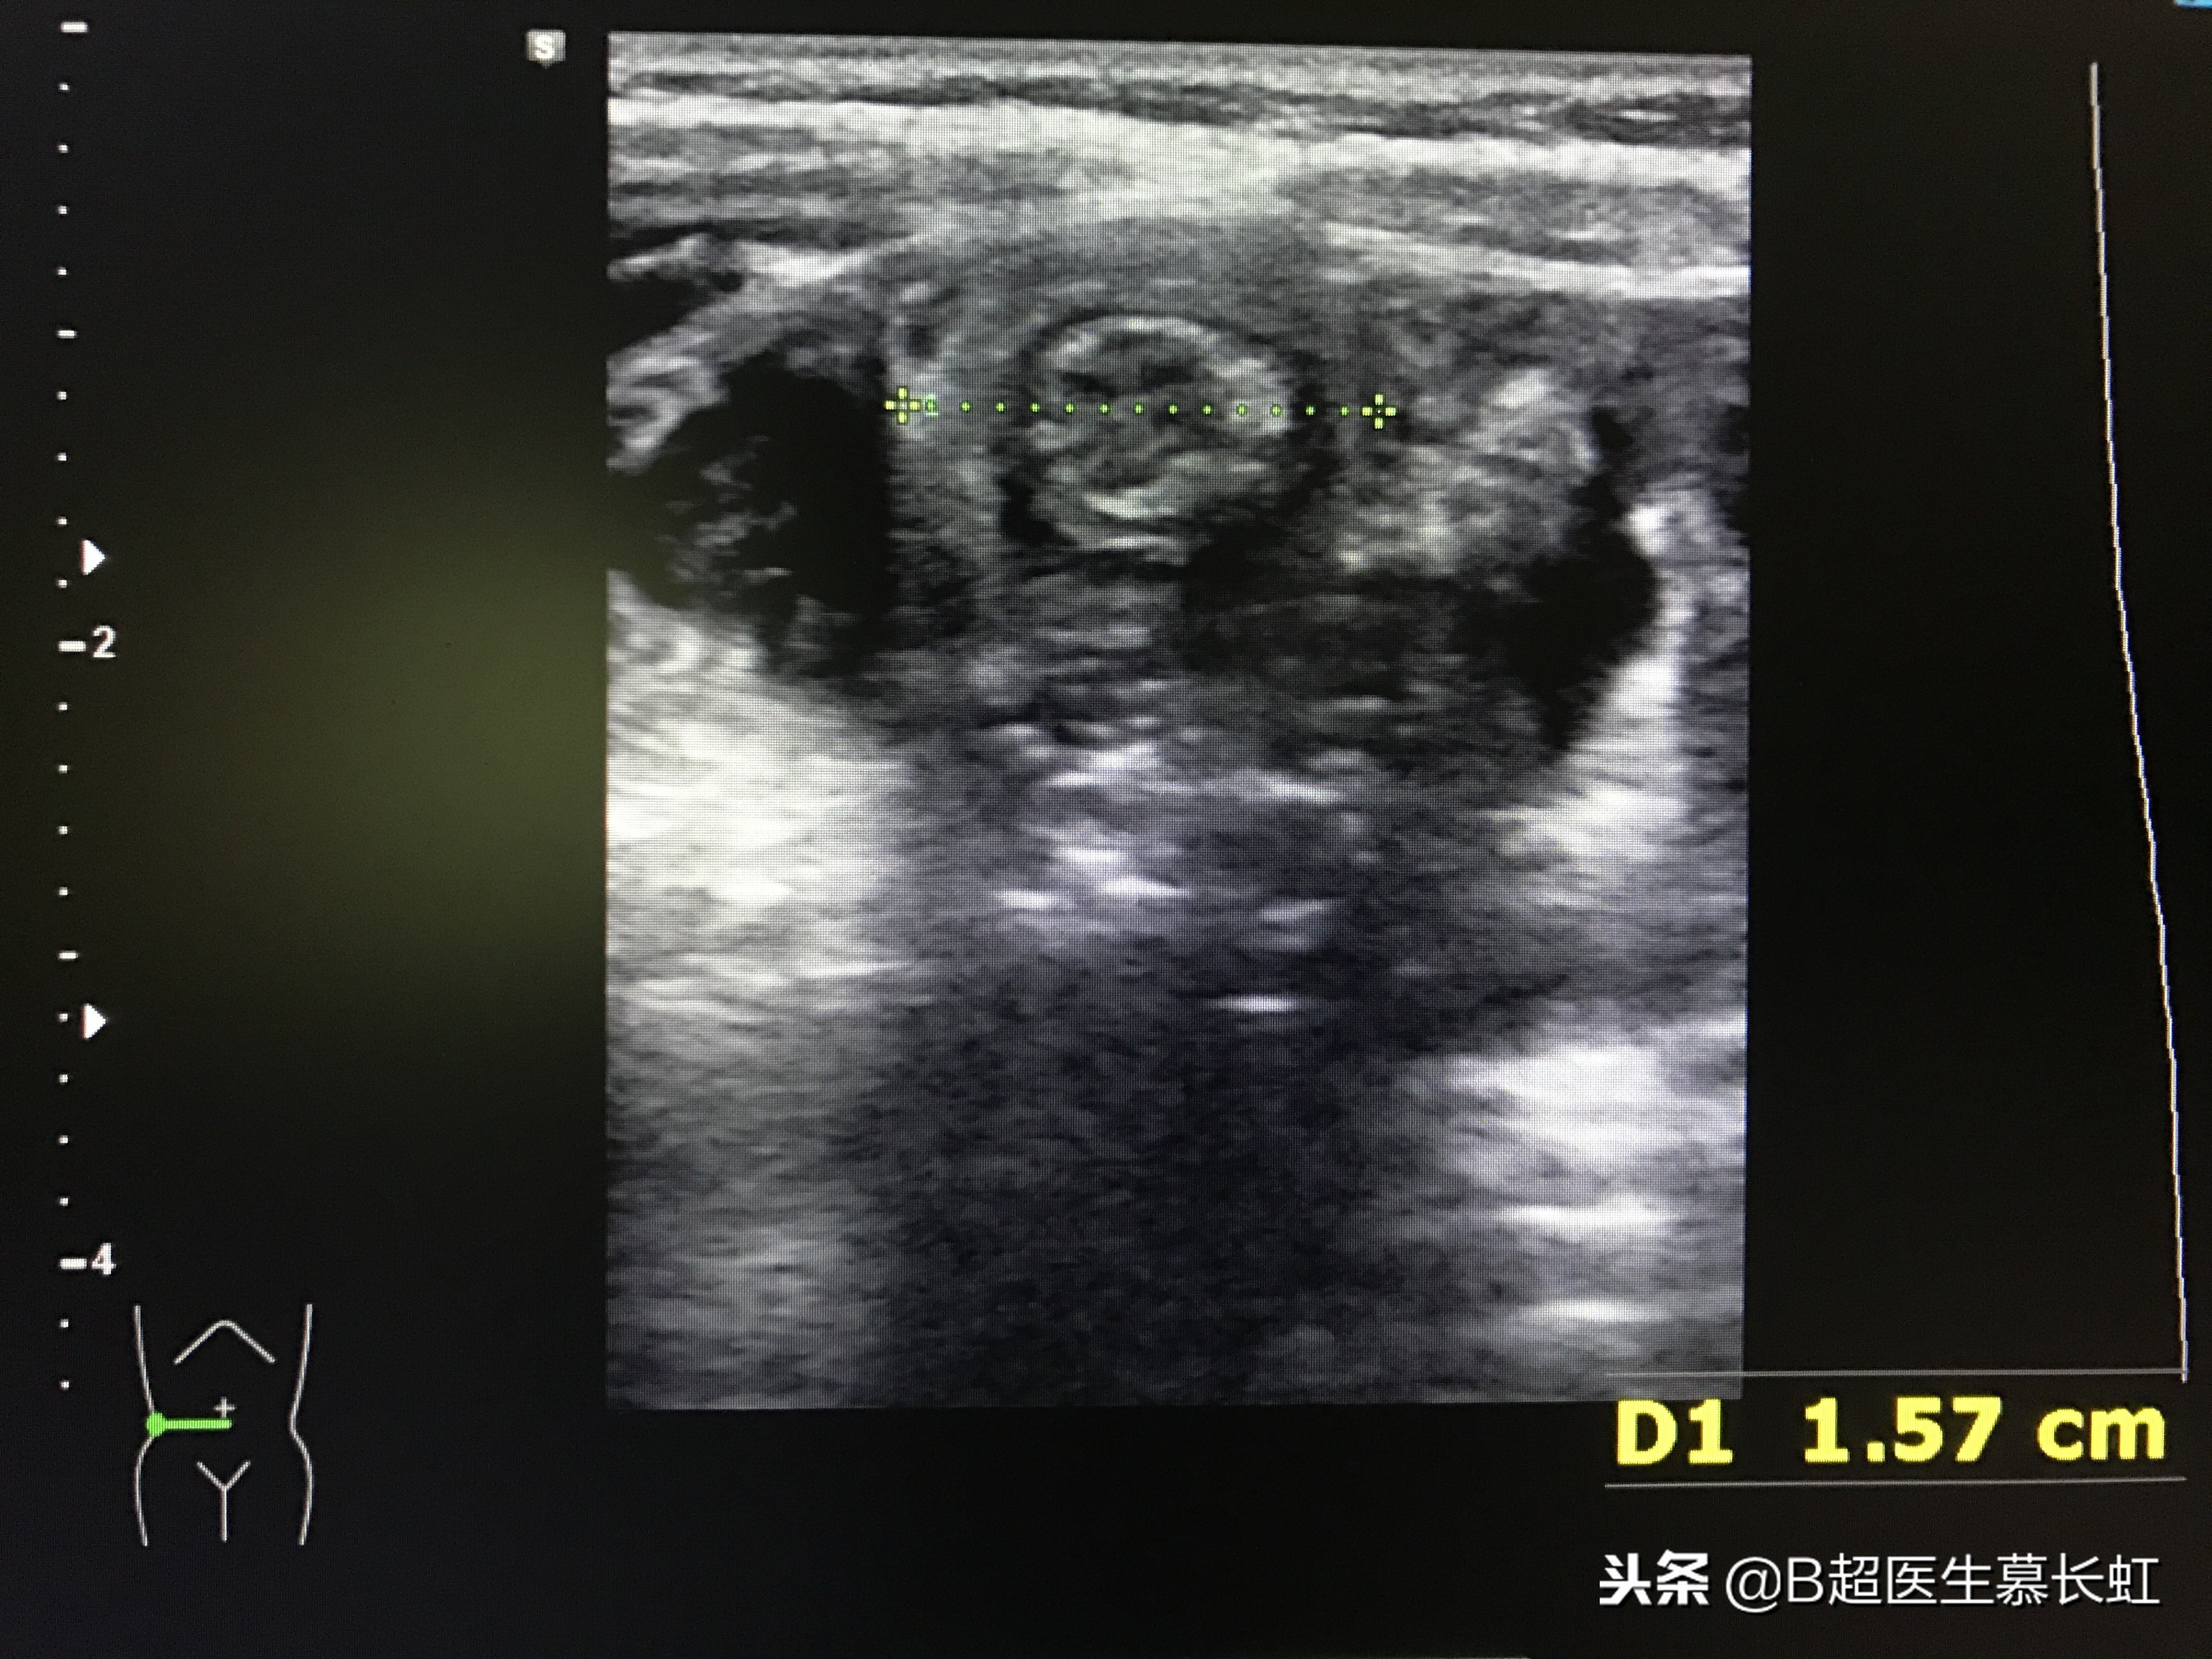

但给这四个小朋友做超声检查,扫查腹部时,均在脐周发现肠套叠。

超声表现:1、同心圆征:肠壁水肿不严重。

2、炸面圈征:外层肠壁水肿增厚。

3、炸面圈内新月征:内部有套入肠系膜。

同心圆征,两处肠套叠